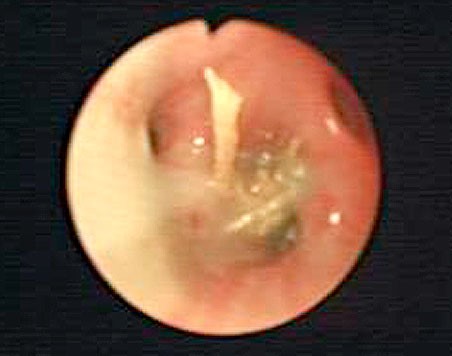

Head shaking: The seeds can enter the ears often causing a sudden onset of head shaking on a walk. Sometimes the seeds will get caught in the hair around the ear and then slowly migrate into the ear canal at a later date causing intense irritation and infection to develop.

- Ears can generally be relatively readily removed using a long pair of crocodile-type forceps